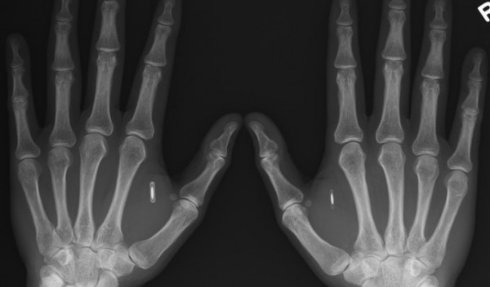

Согласно имеющейся информации, в каждую руку энтузиаста, между кожей и мышечной тканью ладоней, специалисты имплантировали модули связи ближнего поля — устройства заключены в миниатюрные стеклянные капсулы.